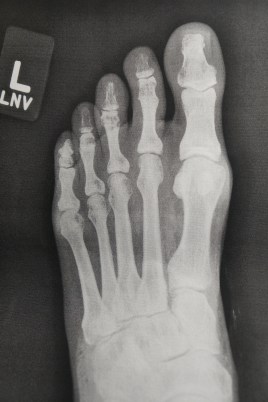

Hammer Toe

Some digits don’t show on x-rays here since they are so stacked up.